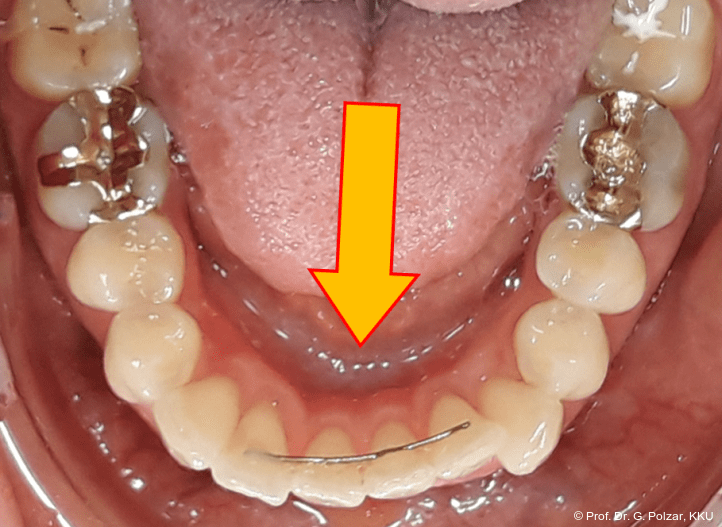

Anamnestisch ist eine Tonsillektomie im Kindesalter und ein ausgeprägtes atypisches Schluckmuster mit typischer mentaler Hyperaktivität zu erwähnen (Abb. 2)

Der intraorale Befund zeigte eine scheinbar neutrale Verzahnung. Trotz Lingualretainer in der UK-Front war ein Engstand in der Unterkieferfront mit leichter Protrusion erkennbar. Appro­ximal des Zahnes 41 waren deutliche schwarze Dreiecke zu erkennen, zudem wies der Zahn eine leichte gingivale Rezession auf (Abb. 3a–f).